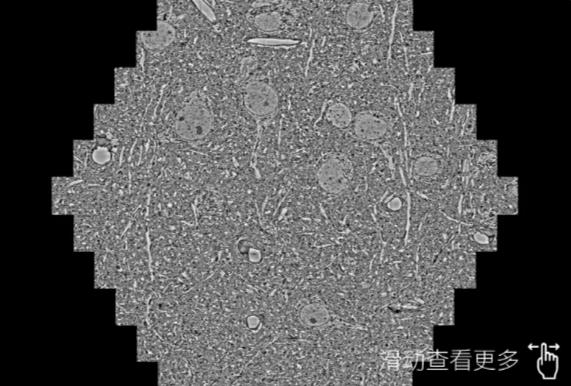

鼠脑切片。左图使用衢州蔡司衢州扫描电镜MultiSEM706对165μmx143pm面积区域成像,耗时仅需1.5秒。右图为鼠脑切片中30μm区域放大效果。样品由芝加哥大学B.Kasthuri提供。